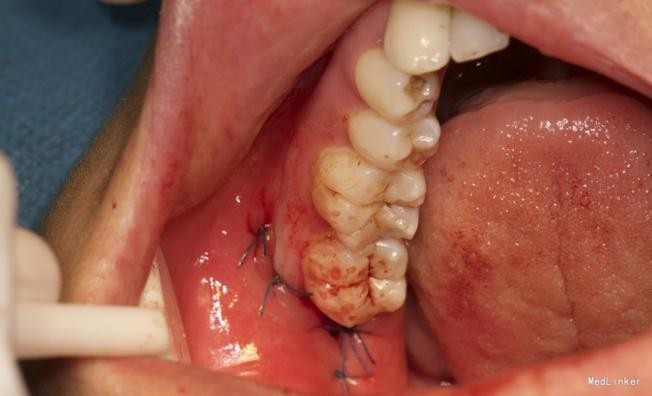

左下8水平阻生拔除

拔除术

效果很好,患者满意